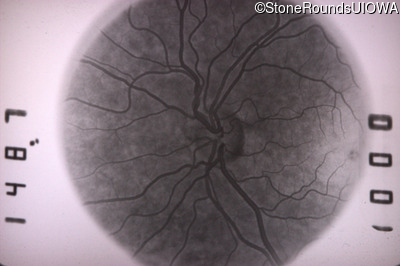

Infrared Fundus Photograph - Right - 20/40 -1

Exemplar